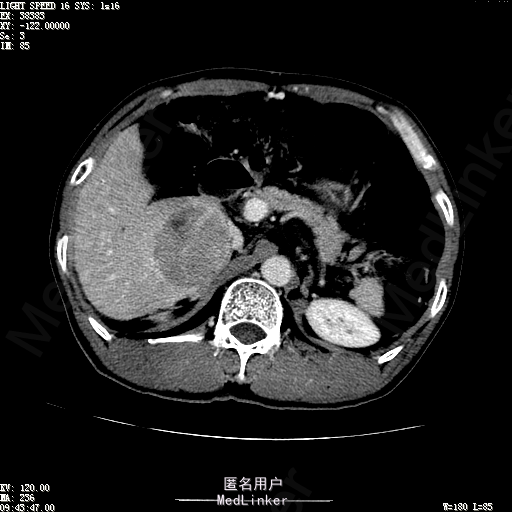

查体:体温36.4℃,脉搏76次/分,呼吸18次/分,血压110/70mmHg。神志清晰,发育正常,营养中等,体位自如,表情安静,慢性病容,检查合作。皮肤粘膜颜色正常,无瘀点、紫癜,有肝掌,无蜘蛛痣,无水肿,毛发的生长与分布正常。浅表淋巴结浅表淋巴结未触及肿大。无巩膜黄染,结膜正常。口唇红润,粘膜正常,舌正常,牙龈正常,扁桃体无肿大,无咽部充血。颈部外形对称,颈静脉正常,肝颈静脉回流征阴性,气管居中。甲状腺正常,无颈部血管杂音。胸部形态正常,呼吸运动平稳规律,无呼吸困难,肋间隙正常。触诊语颤正常,无胸膜摩擦感,肺下界位于右锁骨中线第六肋间。呼吸音正常,未闻及干湿啰音,无胸膜摩擦音。无心前区隆起,心尖搏动正常,心率:76次/分,心律齐,心音正常,无杂音,无心包摩擦音。无大动脉及周围血管征,无奇脉及交替脉,无水冲脉,无枪击音,腹型对称,无腹壁静脉曲张,未见胃肠型及蠕动波,无瘢痕,脐部正常。无压痛,无反跳痛,无腹肌紧张,无腹部包块。肝未触及,Murphy征阴性,脾未触及,肾未触及,无移动性浊音。无肝区叩击痛,无肾区叩击痛,无脾区叩击痛。肠鸣音正常4次/分,无气过水声。外阴及肛门:未查。四肢正常,关节正常,无下肢水肿,无下肢静脉曲张,无杵状指趾。 辅助检查:彩超:肝表面欠光滑,肝内占位5.2*5厘米 ct如下图

诊断:乙肝肝硬化 代偿期 原发性肝癌。 患者病史明确,目前化验转氨酶轻度升高,说明有活动性肝损伤,白蛋白降低提示肝脏合成代谢功能下降,AFP从一年前至今逐渐升高,提示活性肿瘤细胞增多。CT所见明确诊断肝癌,并有周围卫星灶,应近期行TACE治疗。 处置:DSA下肝动脉造影及TACE 手术简要经过:患者平卧位,术区皮肤消毒,铺手术巾,2%利多卡因局麻后,Seldinger法穿刺右股动脉,入血管鞘,5F猪尾管腹主动脉造影,超滑导丝yidao5F RH管腹腔干、肠系膜上动脉、左肾动脉分别造影,腹腔干造影时,见肝右叶7-8处小结节样肿瘤染色,未见外凸生长较大病灶染色。微导管超选肝右动脉注入三氧化二砷碘油混悬液10毫升,横结肠遮挡部位见较大病灶有伞状碘油沉积。复查造影未在见肿瘤染色,拔出导管和血管鞘,穿刺处压迫止血,加压包扎。术毕。

患者术后8天来,无不适,无发热,无腹痛和腹胀,无恶心呕吐,食欲睡眠好,尿便正常。 查体:神志清,巩膜无黄染,心肺听诊无异常,腹软,无压痛,肝脾肋下未触及,移动性浊音阴性,双下肢无浮肿。 复查化验结果:丙氨酸氨基转移酶 116 U/L、天门冬氨酸氨基转移酶 41 U/L、胆碱酯酶 1995 U/L↓、总蛋白 56.3 g/L、白蛋白 25.9 g/L。白细胞计数 5.8 10^9/L、红细胞计数 3.18 10^12/L、血小板计数 175.0 10^9/L、*血红蛋白 83 g/L、血小板分布宽度 15.7 、血小板压积 0.175 %、*红细胞压积 24.6 %、平均红细胞血红蛋白 26.1 pg、平均红细胞血红蛋白浓度 337.0 g/L、平均红细胞体积 77.5 fL、平均血小板体积 10.0 fL、嗜碱性粒细胞百分比 0.4 %、嗜碱性粒细胞数量 0.02 10^9/L、中性粒细胞百分比 70.4 %、中性粒细胞数量 4.10 10^9/L、嗜酸性粒细百分比 2.1 %、嗜酸性粒细胞数量 0.12 10^9/L、单核细胞百分比 12.2 %、单核细胞计数 0.7 10^9/L、淋巴细胞数量百分比 14.9 %、淋巴细胞计数 0.9 10^9/L。甲胎蛋白 23564.00 ng/mL 患者术后第8天开始行FOLFOX6化疗。CT上可见明显碘油沉积,术后甲胎蛋白下降治疗有效。嘱患者术后必须定期复查